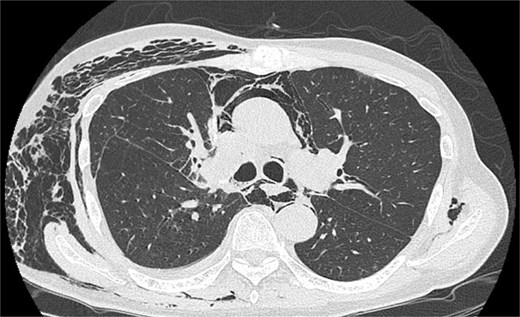

After the reoperation, AL was not observed, and SE regressed. The chest tube was removed on POD 5 after the reoperation (POD 16 after initial surgery). The patient was discharged on POD 18 after initial surgery. CT performed after 1 year revealed no emphysema or cancer recurrence (Fig. 3). The patient was informed of the complications and accepted the treatment outcomes.